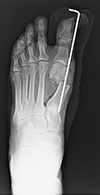

外反母趾とは、足の親指(母趾)が、第2趾の方へ曲がって変形している足の変形です。

母趾の付け根の内側の痛みを生じる場合が多く、バニオンと呼ばれる胼胝(たこ)を形成することもあります。親指の症状だけでなく、第2趾や第3趾の足底痛や足の甲の痛みを生じることもあります。

外反母趾の手術法は100種類以上あるといわれていますが、当院では患者さんへの侵襲の少ないDLMO(デルモ)法という第1中足骨遠位骨切り術を行っています。この術式は約2cmの皮膚切開で、第1中足骨を骨頭基部で骨切りしたのち、骨片間を鋼線1本で止めるというシンプルな術式です。鋼線は手術後1か月で抜去するので、術後に体の中にインプラント(金属)が残らないこともこの術式の特徴といえます。